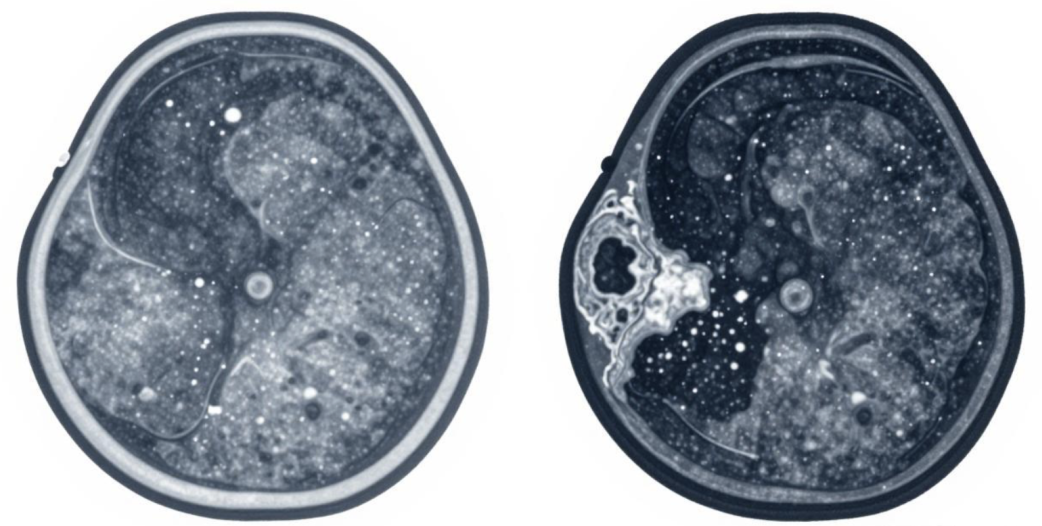

一、分级才是风险判断标尺

乳腺结节的大小,只能说明结节的尺寸,和良恶性没有绝对的对应关系。临床上常有小尺寸但风险高的结节,也有大尺寸但完全良性的结节。真正能科学评估结节恶性风险的,是国际通用的BI-RADS分级,从0到6级,级别越高,恶性可能性越大。

4级:可疑恶性,需要重点关注,进一步检查明确;

5-6级:高度怀疑或已确诊恶性,需及时干预治疗。